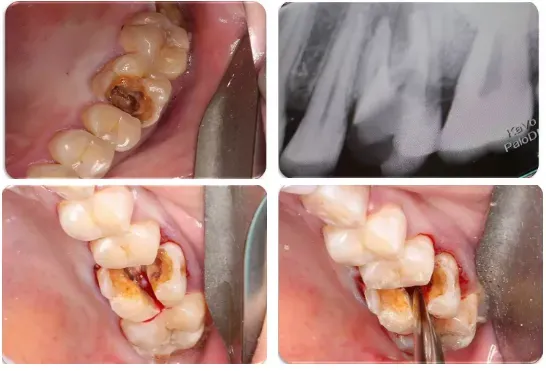

5、下颌第三磨牙的阻力分析及手术设计;

●怎样正确读懂X线片和CBCT上关于下颌第三磨牙的信息

●下颌阻生第三磨牙的阻力分析、解除各步骤要点

●通过病例讲解各类下颌阻生第三磨牙的微创拔除方法

●通过病例分析手术中遇到问题怎样解决